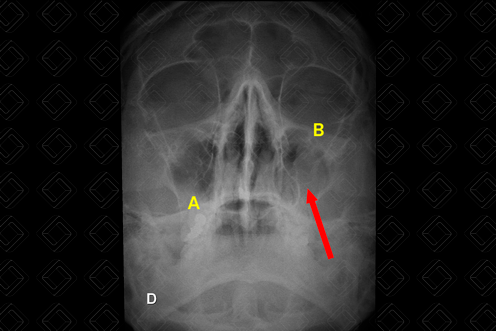

Texto alternativo para a imagem Figura 2. Radiografia dos seios da face fronto-naso AP. Créditos: Dra. Elazir Mota - Rio de Janeiro/RJ

Legenda das siglas (figura 2): A = seios frontais; B = órbita; C = seios maxilares; D = células etmoidais anteriores.

• Incidência de Caldwell (posteroanterior em fronto-naso): Colocar o nariz e a testa do paciente contra o Bucky vertical ou a mesa com o pescoço estendido. Permite avaliar os seios frontais projetados sobre a sutura frontonasal. Células aéreas etmoidais anteriores visualizadas laterais a cada osso nasal, diretamente abaixo dos seios frontais. (Vide Figura 2 acima, em "Como Solicitar") ;